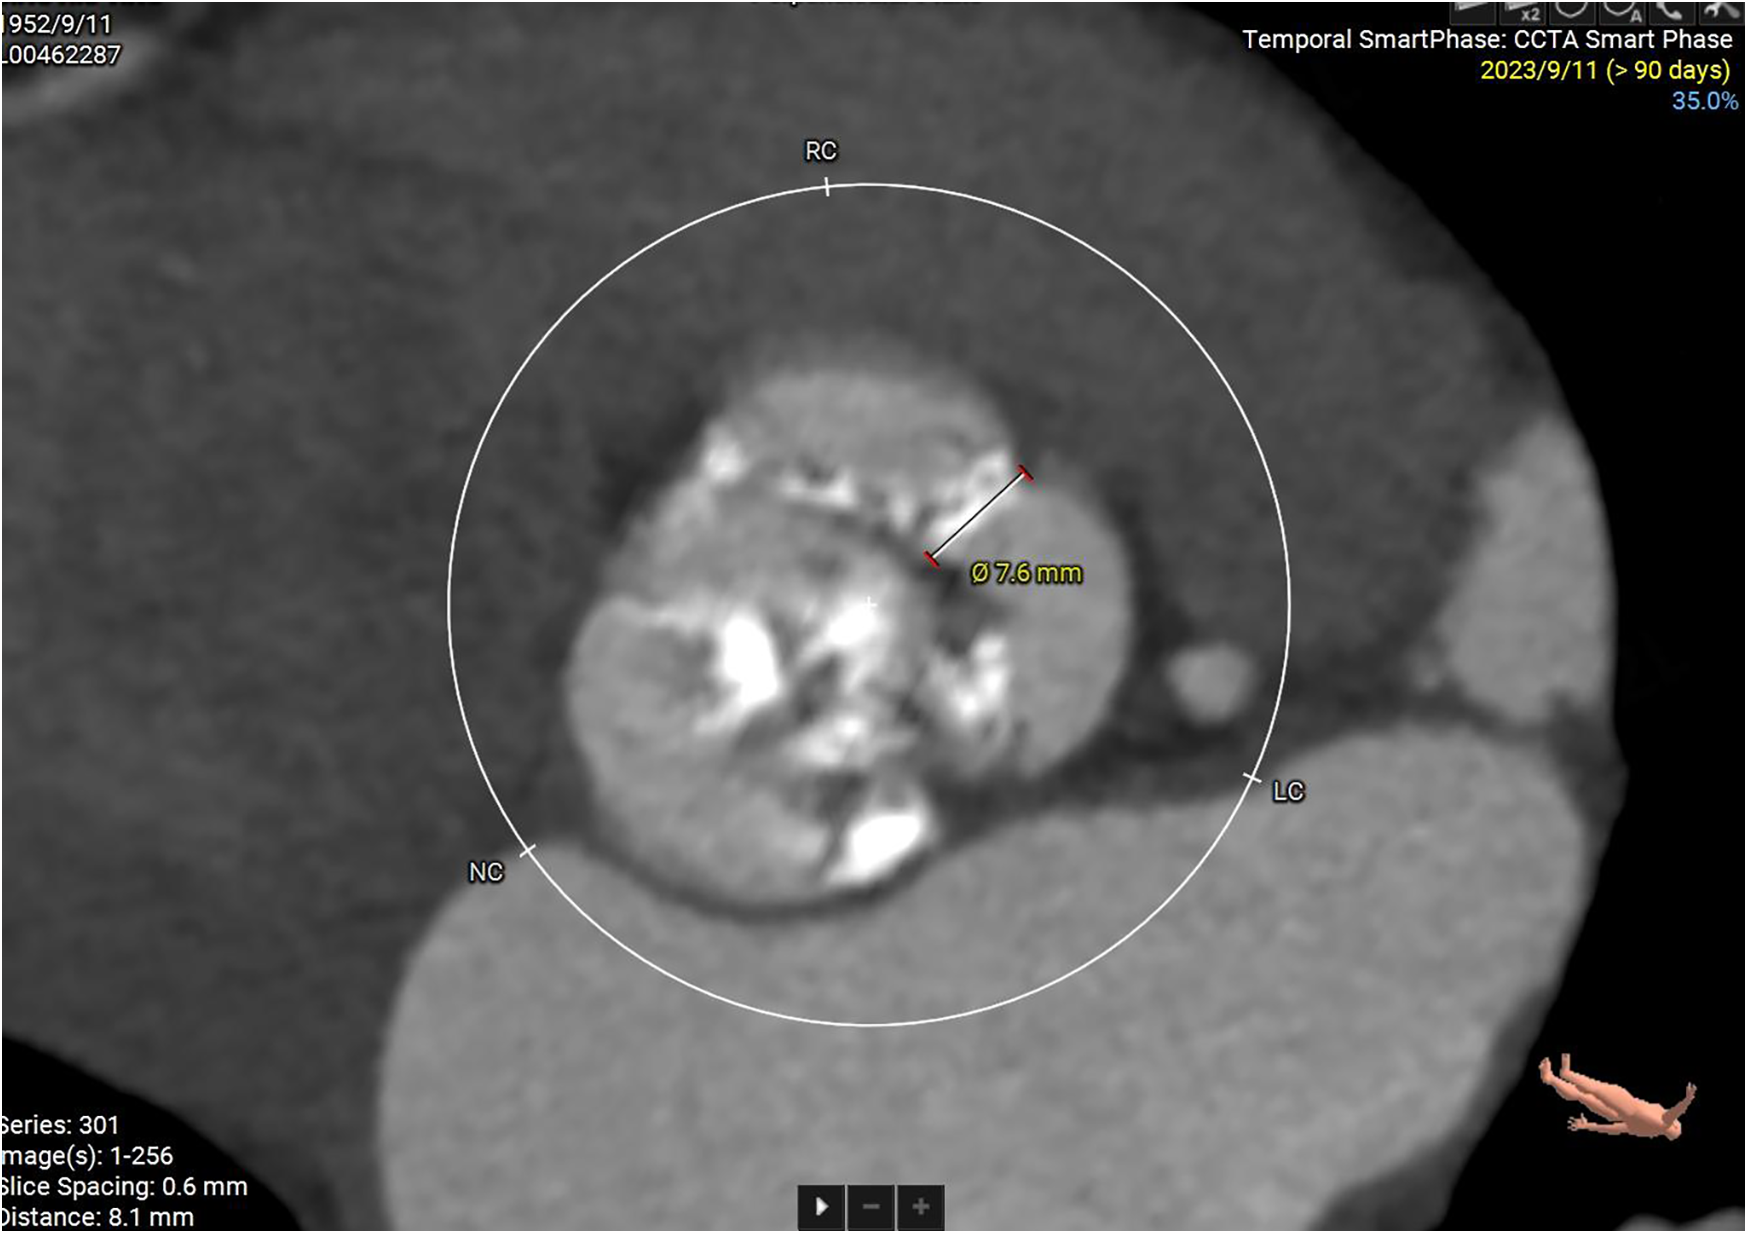

Some important biochemical test results of this patient were presented in the Table 1. Other biochemical indicators, including liver function, electrolytes, coagulation function, and glycated hemoglobin were all within the normal range. The electrocardiogram revealed that she had a sinus rhythm, with ST segment depression ranging from 0.05 to 0.10 mV in leads V3–V6, accompanied by T wave abnormalities. Our hospital's echocardiography results were also listed in the Table 1. The echocardiography conclusion indicated severe AS accompanied by mild regurgitation and the aortic valve was bicuspid aortic valve. The pre-TAVR enhanced CT scan demonstrated that the patient had a Type-1 bicuspid aortic valve with L-R fusion, and the thickness of the fusion raphe was 7.6 mm (Figure 1). All other important data of enhanced CT were listed in the Table 1. The calcification score of the valve leaflets was 723 mm3 and the valve orifice area was small, indicating poor leaflet coaptation, compromising their mobility and a high risk of paravalvular leak (Supplementary Video S1). Notably, both common iliac arteries were congenitally thin along their entire lengths. The thinnest part on both sides measured approximately 5.0 mm, and no atherosclerosis was observed (Figure 2). The remaining portions of the abdominal aorta and ascending aorta were normal. The minimum internal diameter of the right carotid artery was 5.0 mm, and that of the left was 5.6 mm (Figure 2). Taken together, the patient's diagnosis was severe AS with mild regurgitation, and the cardiac function was classified as class I. After a thorough evaluation, valve replacement was needed for this patient. The patient and their family opted for TAVR instead of SAVR. However, the TAVR procedure presented certain challenges. The peripheral vascular access was extremely narrow, potentially making it unsuitable as a route for the large TAVR sheath. Furthermore, the aortic valve showed severe calcification and had a small valve area, significantly limiting their mobility. This indicated a considerable difficulty in the retrograde crossing of the valve through the aorta with a guidewire. Our TAVR procedure comprised two key steps: firstly, establishing an artificial vascular-common iliac artery approach, and secondly, proceeding with anterograde atrial septal puncture if the retrograde transaortic approach was unsuccessful.

Figure 1

Enhanced CT examination of valve characteristics.